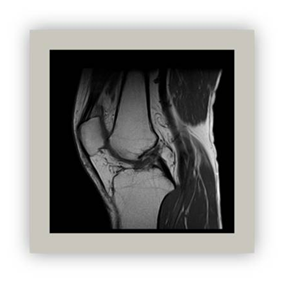

Magnetic resonance

This method based on applying radio waves to a magnetic field. It provides an important image of the central nervous system and musculoskeletal soft tissues (Figure 5 & Figure 6).28‒31

Figure 6 The right knee MR T1 TSE sagittal section.